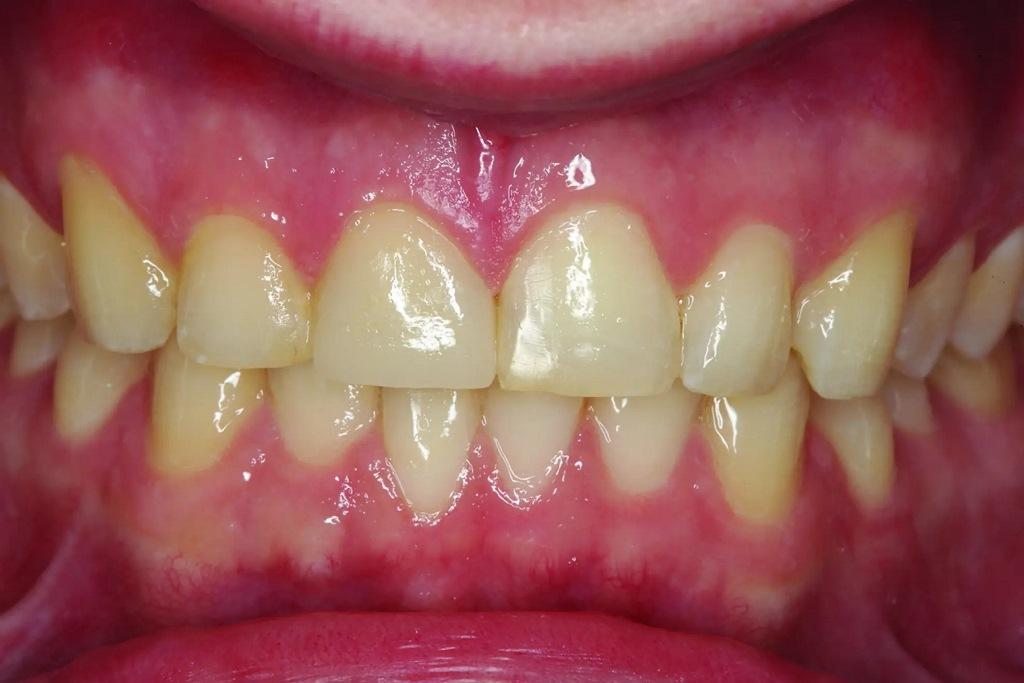

А как насчет выравнивания зубов-антагонистов? На режущих краях зубов 31 и 41 (фото 2) наблюдался чрезмерный износ. Со стороны резцов был виден значительный износ всех краев нижней челюсти из-за окклюзионного заболевания, которое часто наблюдается, но не лечится (фото 3). Также зуб 41 располагался на лицевой стороне таким образом, что при выступающей экскурсии он преждевременно соприкасался с небной поверхностью зуба 11, создавая дополнительную нагрузку как на небную поверхность, так и на резцовый край зуба 11, прежде чем соединиться с остальной частью переднего сегмента верхней челюсти. Это демонстрирует, что решение этих проблем реставрационными методами включает в себя нечто большее, чем просто исправление сколов композитной реставрации.

Фото 3: Резцовый вид показывает, что зуб 41 был наиболее расположенным к лицу резцом нижней челюсти в форме дуги.